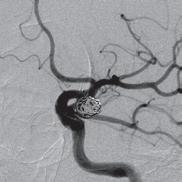

“This is a good example of a problem I’m having clinically that’s being solved by our research group,” says radiologist and scientist, Shane Wells, MD, Associate Professor of Radiology and Urology whose research focuses on improving diagnostic information to help urologists make more informed decisions. “I currently use ultrasound or CT to put needles into the liver to treat tumors. The needles get hot at the end and burn the tumor. It’s a minimally invasive procedure that can actually cure liver cancer and patients can go home the same day. However, one of the shortcomings of the current technology is that we can’t target tumors very well, which negatively affects patient outcomes. Now, the platform that we’ve developed at MIITT combines ultrasound and MRI to improve that tumor targeting.”